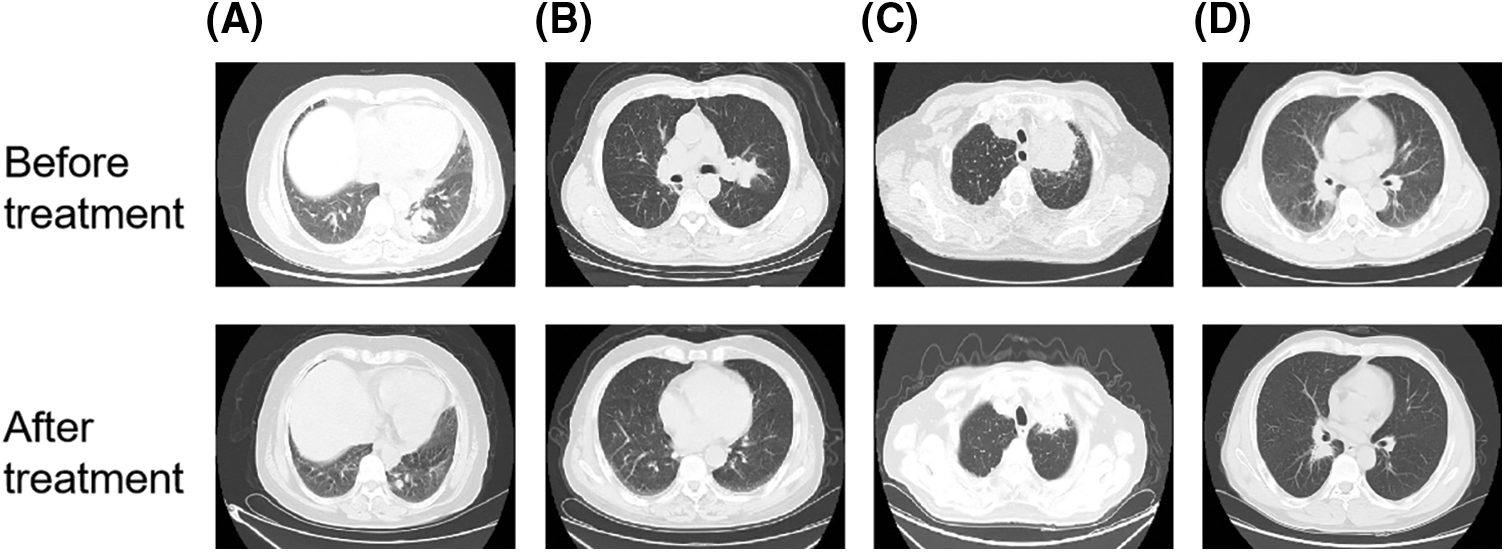

3.4 QYSL Combined with Anti-Tumor Agents Significantly Prevented Tumor Progression in Clinical

QYSL is a commonly used and important formula for the treatment of lung cancer in our department, which has been proved to have good anti-tumor effect. In this study, we share four clinical cases.

A 61 years old female patient had cough and expectoration for more than 2 months. Chest enhanced computed tomography (CT) showed a space occupying lesion in the lower lobe of the left lung, considering lung cancer, with multiple metastasis of mediastinum, bilateral hilar and bilateral supraclavicular lymph nodes. The pathological results showed that the metastatic small cell carcinoma of the right supraclavicular lymph node was likely to originate from the lung. Immunohistochemical results were CK (+), CK7 (−), TTF-1 (+), napsina (−), CK5/6 (−), p63 (−), p40 (−), NSE (+), CD56 (+), CGA (−), syn (+), Cdx-2 (−), CK20 (−), ALK (−), Ki67 (60% +). This patient had received a regimen with Etoposide injection 0.1 g for 9 days, Carboplatin Injection 300 mg for 3 days, combined with Sintilimab 200 mg immunotherapy and QYSL prescription. Finally, this patient was in partial remission (Fig. 4A).

Figure 4: QYSL combined with anti-tumor agents significantly prevented tumor progression in clinical. (A–D) CT image comparison of lung cancer patients before and after combined treatment with QYSL

A 73 years old male patient went to Anhui provincial hospital because no obvious inducement to lose weight. Chest and abdominal CT showed that the right upper lobe mediastinum was occupied with obstructive pneumonia. Considering the possibility of tumor, further examination is recommended. The pathological results of bronchoscopy showed that scattered heterology epithelial cells were found, which was consistent with squamous cell carcinoma. Immunohistochemical results were p40 (+), CK7 (−), TTF-1 (−), Ki67 (60% +). After that, radiotherapy for lung lesions and lymphatic drainage area was started. Gross tumor volume (GTV): 6000cGy/30f, 200cGy/f. The patient received radiotherapy for 22 times and refused to continue radiotherapy because adverse radiation reactions. After discharge, the patient went to our outpatient department for intermittent QYSL prescription treatment. On August 03, 2020, the patient rechecked chest CT. The results showed that the right lung cancer with right pulmonary obstructive pneumonia had unclear boundary with the superior vena cava, and the mass shrank. On August 12, 2020, the patient was admitted to our department. Considering that the patient was lung squamous cell carcinoma and the gene test was negative, the patient had received a regimen with recombinant human endostatin 210 mg 2 ml/h micropump, tegafur bid d1-21, Sintilimab 200 mg, combined with QYSL prescription. Finally, This patient was in partial remission (Fig. 4B).

The 84 years old male patient had chest pain without obvious inducements, which was more obvious on the left. Chest CT showed a space occupying lesion in the posterior segment of the upper lobe tip of the left lung (maximum diameter 5.9 cm), considering lung cancer. On September 02, 2021, the patient was admitted to our department. Lung puncture pathology showed that it was squamous cell carcinoma. After consultation, the thoracic surgery and radiotherapy department would consider that the patient was old, with chronic bronchitis, emphysema and pulmonary bullae, which was not suitable for surgery and radiotherapy. The gene detection showed that there was no mutation in EGFR, ALK, ROS1, and NTRK. Then, this patient had received a regimen with Tislelizumab 100 mg d0, ENDOSTAR 210 mg was continuously micropumped for 7 days Q3W, combined with QYSL prescription. Finally, this patient was in partial remission (Fig. 4C).

A 58 years old male patient coughed and expectorated for more than 1 month. Bronchoscopy showed that new organisms blocked the lumen of the middle bronchus of the right lung. The new biopsies of the middle bronchus of the right lung were sent for pathological examination. The results showed that it was moderately to poorly differentiated squamous cell carcinoma. Immunohistochemical results were CK (+), p63 (+), p40 (+), CK5/6 (+), CK7 (−), TTF-1 (−), napsin-a (−), Ki67 (70% +), ALK (d5f3) (−). This patient had received a regimen with ENDOSTAR continuous micropump, Tislelizumab 200 mg ivgtt, tegafur 40 mg bid po, anti-vascular combined with immune regimen, combined with QYSL prescription. The patient was in stable condition during treatment (Fig. 4D).

Overall, the clinical application results show that the combination of QYSL and other drugs can achieve better clinical therapeutic effect. And because of the strengthening effect of traditional Chinese medicine, the side effects of patients treated with QYSL are significantly reduced.